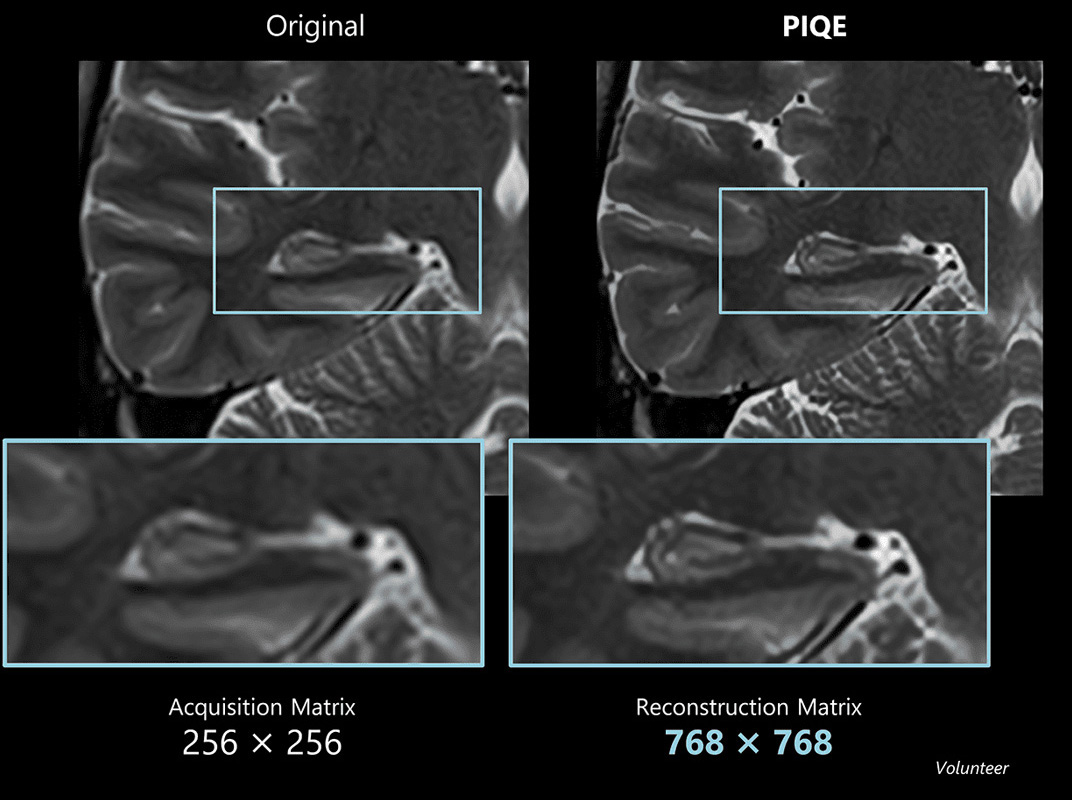

Cor T2w for hippocampus

Example of a high-resolution image of the hippocampus using Precise IQ Engine (PIQE). The original image is 256 matrix with low resolution and high signal-to-noise ratio (SNR).

Even though the scan time is reasonably short and the slice thickness is as thin as 2 mm, the image is clear and demonstrates good contrast.